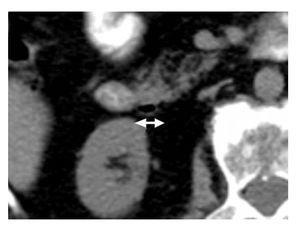

En 43 casos (86%) se evidenció Dd único: un caso (2%) en la primera porción, 13 (26%) en la segunda, 24 (48%) en la tercera y cuatro (8%) en la cuarta porción duodenal En ocho pacientes (16%) se identificaron Dd múltiples: siete casos (14%) en la segunda y tercera porciones y un caso con Dd concomitantes con divertículos yeyunales En 16 pacientes (27%) se encontraron divertículos colónicos concomitantes. El diámetro promedio de los Dd fue de 2.5 cm (rango 0.9 cm a 7.1 cm) (Figuras 2 y 3).

¿ Figura 2. Imagen tomográfica de un Dd de 0.9 cm de diámetro.